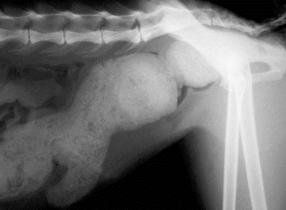

Renal Neoplasia

Et: Primary tumors rare (malignant), renal tubular carcinoma (#1)

Metastasis to chest common

Tx: ureteronephrectomy

only if contralateral kidney fxn